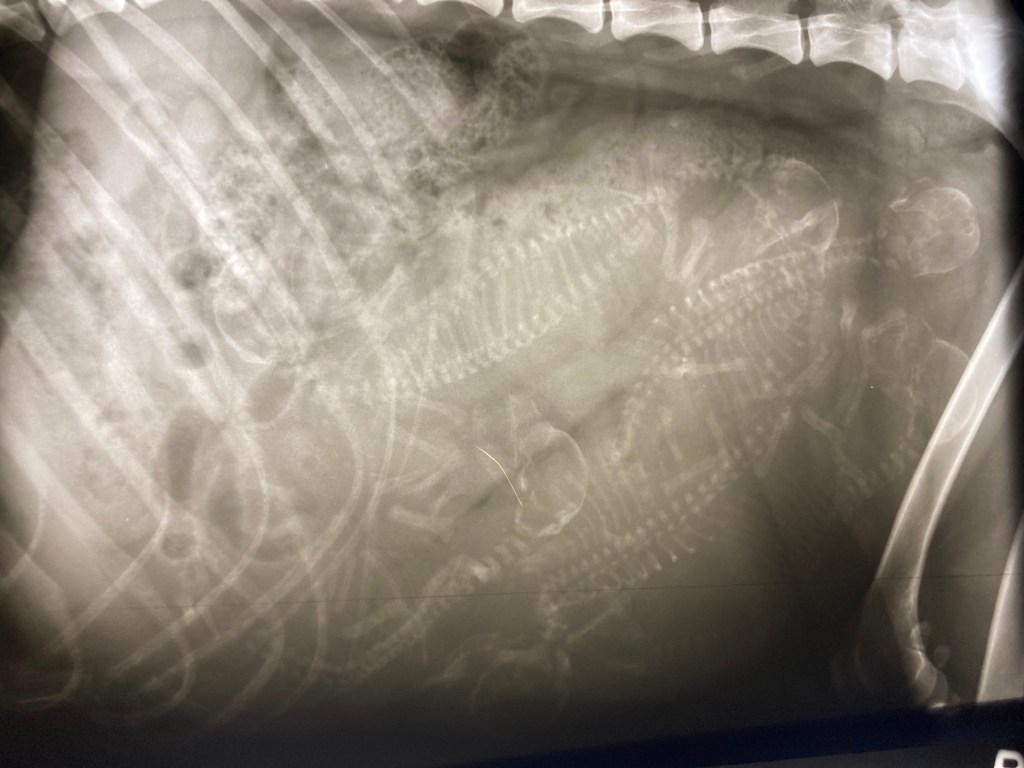

Es hat geklappt und wie erhofft, nicht mehr ganz so viele. Jetzt heisst es abwarten…